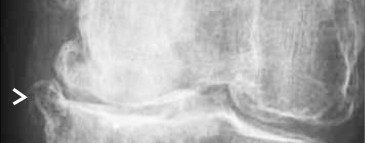

The management of chondral disease poses challenges due to its poor healing potential. Biomechanical and biological changes can accelerate degeneration, leading to end-stage osteoarthritis (OA).

The study, approved by the Ethics Committee, involved 30 patients with diffuse degenerative chondral lesions treated with autologous micro-fragmented adipose tissue between January and December 2014. Clinical evaluations were conducted at 3 years post-treatment.

The study demonstrates sustained benefits of autologous micro-fragmented adipose tissue in treating diffuse degenerative knee chondral lesions at mid-term follow-up, supporting its role as an adjunct in surgical procedures.